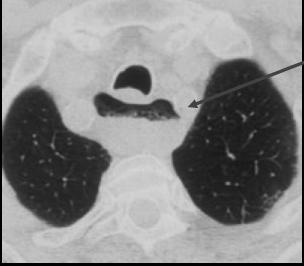

Diverticule epibronchique :

Imges remplie par baryte avec le col est large |

Meme cas

en coupe axiale ( image TDM fenetre parenchymateuse

) . |

Diangostique differentiel

avec duplication kystique de oesophage . Ce qui ne

se remplissant pas en TOGD . Image radiologique TDM

d'une duplicatin kystique de oesoiphage en coupe

axiale ( fleche noire ) |